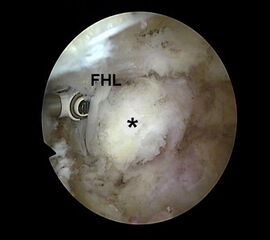

Abbildung Nr. 8-10

Es wird zunächst ein Weichteildebridement durchgeführt, bis die Flexor hallucis longus-Sehne identifiziert werden kann. Während des Debridements sollte auf die korrekte Ausrichtung der Instrumentenöffnung nach lateral geachtet werden. Im Verlauf empfiehlt sich der Wechsel auf eine bipolare Ablationselektrode, die eine gezielte Freilegung der Strukturen unter gleichzeitiger Blutstillung ermöglicht, ohne dabei unkontrolliert Gewebe anzusaugen (rechte Seite, m=medial, l=lateral). Das Os trigonum bzw. die Osteophyten sowie die FHL-Sehne müssen vollständig dargestellt werden (*=Os trigonum, FHL=Flexor hallucis longus-Sehne).